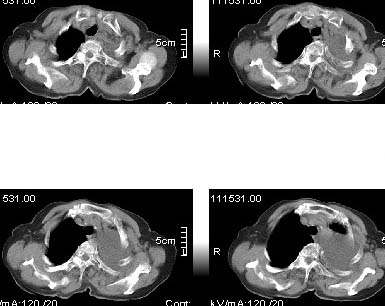

标题: CT4907:[原创]胸部平扫,请讨论!谢谢!!

肝顶部密度是不是不正常?心包有没有积液?胸椎有没有侧弯?

左侧大量胸腔积液伴下叶压迫性且不张,心包积液,左下叶支气管变窄,建议增强扫描,排除占位

左侧大量胸腔积液伴左下肺不张,左侧支气管狭窄,左舌段有膨胀感,中央型肺癌待排,心包有少量液体。肝顶部低密度影,需进一步检查

左侧大量胸腔积液伴左下肺不张,左侧支气管狭窄,左舌段有膨胀感,中央型肺癌待排,心包有少量液体

心包积液.

左肺门未见肿块征象,心包无明显积液表现.

3、心包内脂肪影清晰,未见积液。

左侧胸腔积液,左下肺压迫性不张,建议抽胸水细胞学检查或增强.肝右叶低密度影,建议增强.心包内未见积液征.